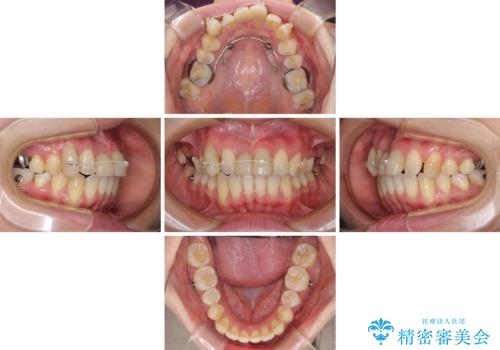

補助装置により上顎歯列を遠心移動させたため、非抜歯でしたが口元の突出感をある程度改善させることができました。

欠けてしまった前歯もオールセラミッククラウンにて自然に補綴することができました。